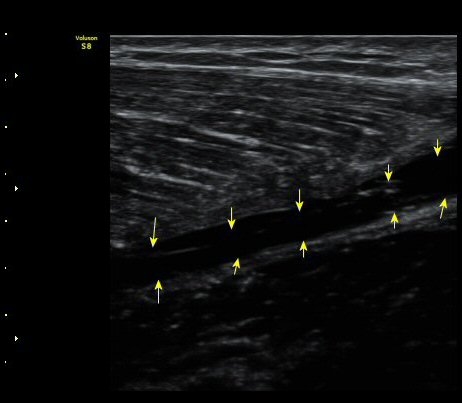

¼ö»ó ÈÄ 2ÁÖ Â°

³»Ãø ºñ·Ï±Ù Á¾´Ü¸é°Ë»ç¿Í Ⱦ´Ü¸é°Ë»ç¿¡¼­ ºñº¹±Ù°ú °¡Àڹ̱ٻçÀÌ¿¡ Ç÷¾×ÀÌ °í¿© ÀÖÀ½

(±×¸² 5, 6, 7).

Ç÷¾× ÈíÀÎ ÈÄ Åº·ÂºØ´ë·Î ¾Ð¹ÚÇÏ¿´´Ù.